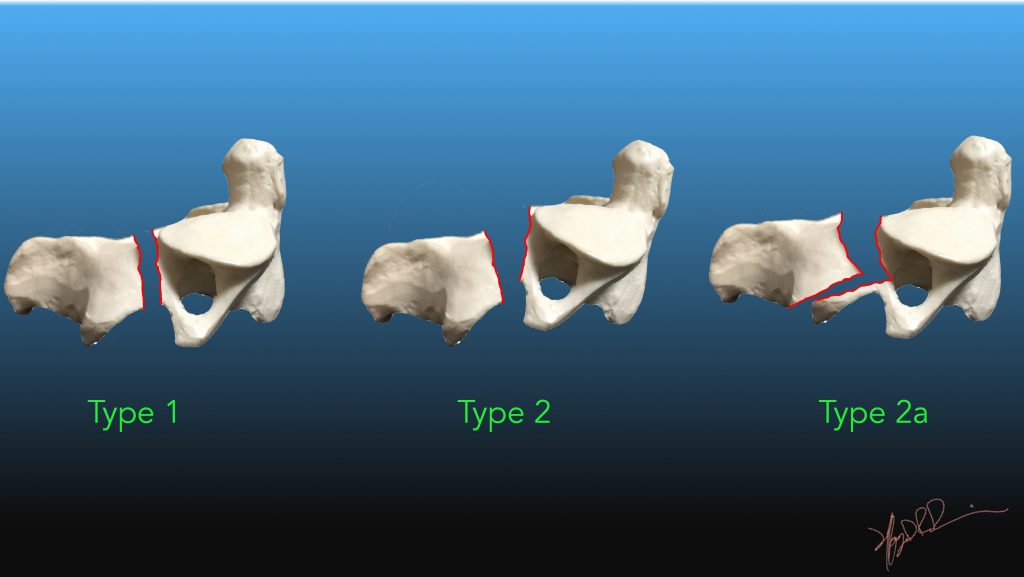

Hangmans Fracture

Hangman's fracture - Wikipedia Hangman's Fracture - Physiopedia Hangman's Fracture, C2 Fracture - Everything You Need To Know - Dr. Nabil Ebraheim - YouTube Hangman fracture | Radiology Reference Article | Radiopaedia.org | Hangmans Fracture